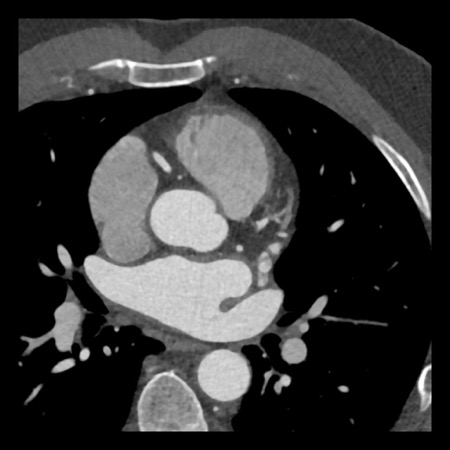

case 1 – CAD-RADS 2/P1

First, scroll through the scan.

Not all images are included. Some images without any abnormalities are skipped

from the series.

How would you describe the findings on the coronary CTA?

The findings are:

- Agatston score of

this patient was 14 (P1). Please, also note the calcification of the aortic valve. - Some partially

calcified and calcified plaques are present in the LAD with mild stenosis

(25-49%). - Calcified-plaque in

the LCX causing minimal stenosis (<25%). - Non-calcified

plaque in the distal RCA causing minimal stenosis (<25%). - This patient classifies

as CAD-RADS 2/P1, which means no further workup is needed.